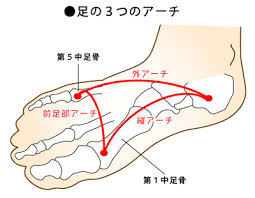

さて、「足の扁平足」がなんとなくいけないというイメージを持たれている方も多いと思いますが、そもそも「足の土踏まず」つまり、「足のアーチ」とは何なのか?について学んでいきたいと思います。

足のアーチとは、、、

- 横アーチ=第1中足骨〜第5中足骨で構成

- 内側縦アーチ=踵骨〜第1中足骨頭で構成

- 外則縦アーチ=踵骨〜第5中足骨頭で構成

となっています。

続いて各アーチの細かい部分を見ていきましょう。

内側縦アーチを構成している骨たちは

- 踵骨

- 距骨

- 舟状骨

- 楔状骨(内側、中間、外側)

- 中足骨(第1〜第3)

外側縦アーチを構成いている骨たちは

- 踵骨

- 立方骨

- 中足骨(第4〜第5)

横アーチを構成いている骨たちは

- 中足骨頭(第1〜第5)